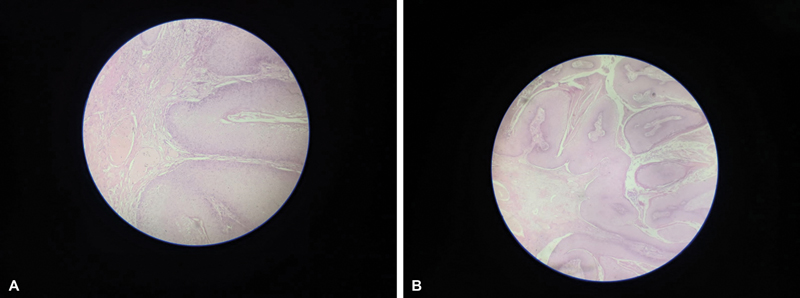

Simple vulvectomy with split skin graft reconstruction was planned after consultation with plastic surgeons. Simple vulvectomy was done ([Fig. 2A]). Vulval reconstruction was performed by harvesting grafts of intermediate thickness from the left thigh and placing them over the excision site ([Fig. 2B]). The plane of dissection was along the line of cleavage. Gross examination of the excised specimen showed a vulval excised flap of 13*9*4 cm with the skin surface showing wart-like growth. The satellite lesions on the thighs, perianal region, and labia minora were separately excised. Postoperative period was uneventful. The diagnosis of condyloma acuminatum with a moderate degree of dysplasia was confirmed by the final histopathology report ([Fig. 3]). Immunohistochemically, it was CD ⅚ positive, p63 positive, and p16 negative. Her functional outcome was good and was disease free even after 13 months postsurgery.

Fig 3 : (A, B) Histopathology image showing papillary proliferation of squamous epithelium with acanthosis and koilocytosis.

Fig 3 : (A, B) Histopathology image showing papillary proliferation of squamous epithelium with acanthosis and koilocytosis.